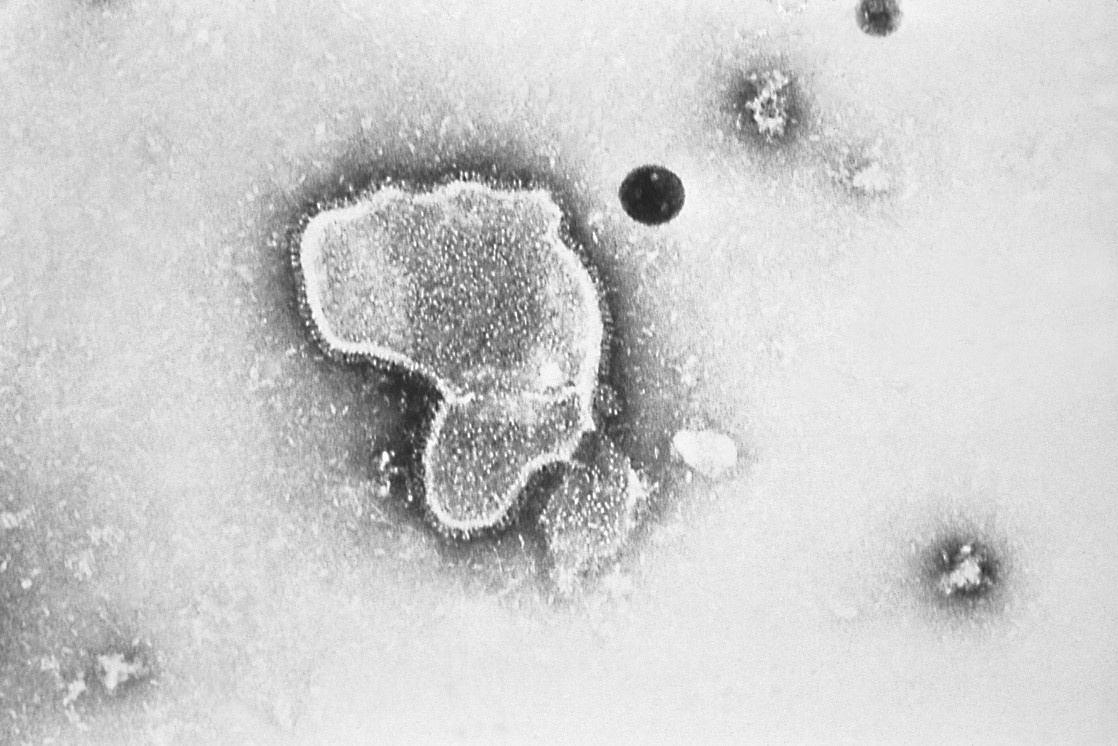

Respiratory syncytial virus under electron microscope. The virion is variable in shape, and size, with an average diameter between 120-300nm

RSV is a single-stranded RNA virus in the genus Pneumovirus that belongs to the Paramyxoviridae family. It is transmitted from humans by respiratory droplets.